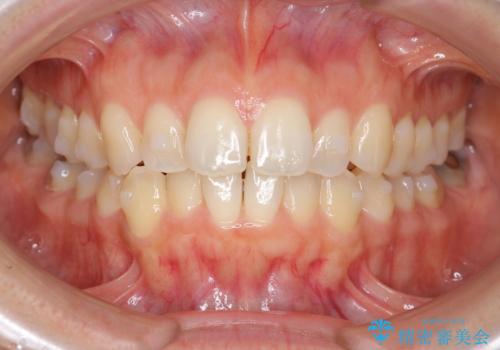

前歯のガタつきをマウスピースで治したい!

- 気になる前歯のガタつきをマウスピースで治療したいと希望され来院されました。

当日に矯正検査を行い、骨格・歯に問題がないことを確認しマウスピースによる矯正治療を進めます。

IPRを前歯部に少量行うことで、非抜歯でも前歯が外に飛び出さない仕上がりを達成できました。